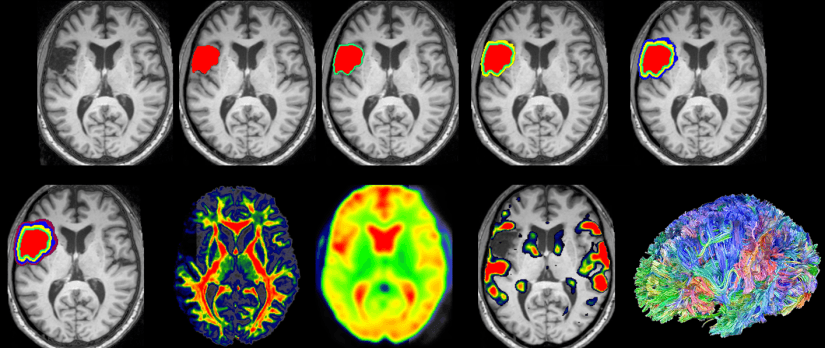

Over the past five years, Fridriksson and his C-STAR team have conducted research to better understand individual responses and recovery for stroke patients who have acute or chronic aphasia. This communication disorder, which affects approximately 30 percent of stroke survivors, results from an injury to the brain that impacts patients’ ability to speak, listen, read and/or write.

Their projects include identifying factors that predict individual responses to different treatments in order to inform clinical management of post-stroke aphasia; providing aphasia therapy and electrical brain stimulation to recent patients to improve the recovery environment in the brain; combining brain imaging and initial testing to accurately predict expected recovery; and comparing neuropsychological models of speech and language in people who have not experienced stroke or injury to those who are recovering. Throughout these four projects, the researchers have collected an abundance of data that they continuously leverage to learn more about new and changing conditions and circumstances, such as how COVID-19 affects the brain.

In the next phase of its funding (i.e., $12.5 million over the next five years), C-STAR will expand its work to include two new clinical trials and two large projects. One of the trials will test whether telerehab is as effective as in-person rehabilitation for aphasia. The second trial will test whether the anti-depressant Escitalopram improves early recovery from aphasia in patients who have recently experienced a stroke. The projects will focus on using artificial intelligence to predict recovery from stroke based on brain health and understanding how language is rooted in the brain.